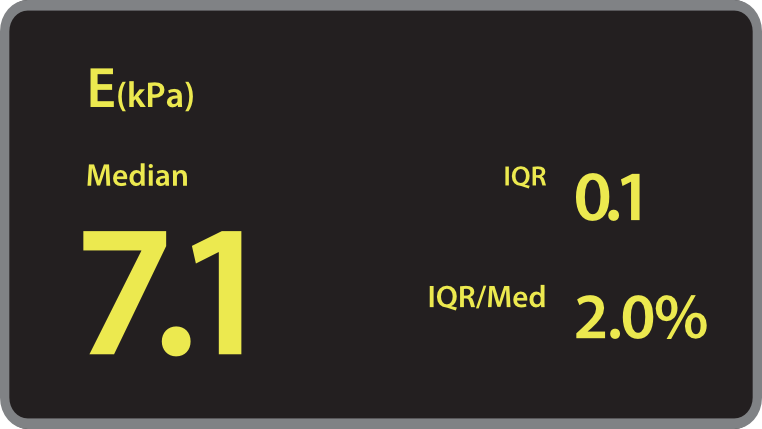

? ??? ?? ???? ???? ?? ???? Hepatus? ? ??? ??? ???? ??? ??? ?????. ???? ????? ??? ? ?? ??? ???? ????? ? ?? ???? ? ?? ??? ??? ??? ?????.

???? ?? ?? ??

??? ???? ?? ? ??? ? ? ???? ?? ??, ??, ???? ? ?? ??? ??? ? ????. ?? ?? ???? ?????.